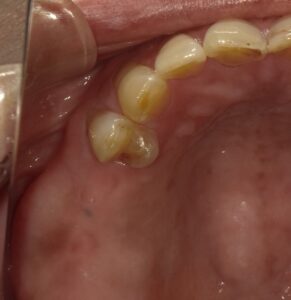

画像のような場合、外から見るだけでは

サイナスリフトが必要かどうかはわかりません。